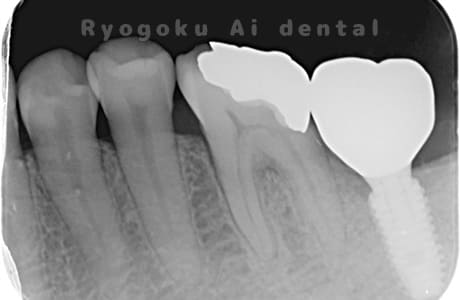

Case07

- 原因

- 右下6番歯根破折

-

- 治療内容

- インプラント治療

- 治療費用

- 約600,000円

右下の腫れが治らないとの事でご来院された患者様です。歯が割れていたため、抜歯を行い、骨に代わるお薬を入れ、インプラントを埋入致しました。経過良好で大変満足していただけました。

<リスク・副作用>

治療後、痛みや違和感、出血、腫れなどが出る事があります。喫煙者、糖尿病などの方の場合、歯が生着しない場合があります。